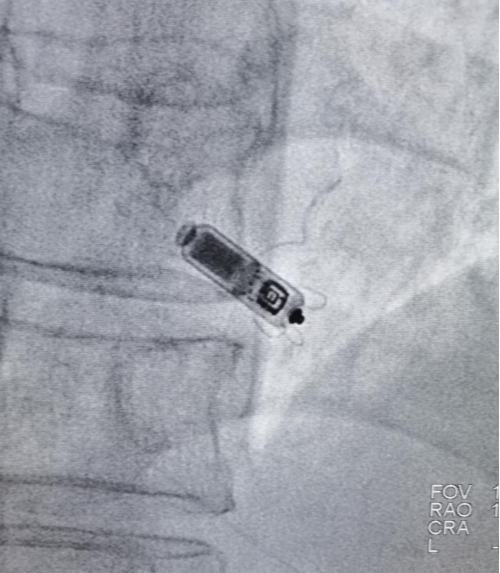

无导线起搏器植入中

根据患者疾病的复杂性,为解决心率慢的问题,心内四区李林锋主任医师团队做好了充分的评估、术前讨论、术前准备后,2021年10月13日,在省心血管病医院院长洪浪的指导下,给患者进行了无导线起搏器植入术。手术仅用时40分钟,无伤无疤痕,微创解难关。术后患者情况良好,生命体征平稳。

心脏内植入的无导线起搏器

知识拓展:无导线起搏器通过全新的设计缩小电子元器件体积最小的起搏器,体积较传统的起搏器减少了92%,只有胶囊大小,所以又称胶囊起搏器。胶囊起搏器虽然个子小,但是功能很齐全,也具备抗核磁功能,寿命也可达十二年以上。无导线起搏植入是通过专用的植入递送系统,采用微创介入技术,通过下肢的股静脉递送到右心室,然后起搏器是通过顶端的小翼直接勾挂在右心室的肌小梁上,实现起搏的功能。不用开刀,无创口,无囊袋,特别适合高龄、瘦小、血小板少、需长期服用抗凝药、易感染的老年患者。